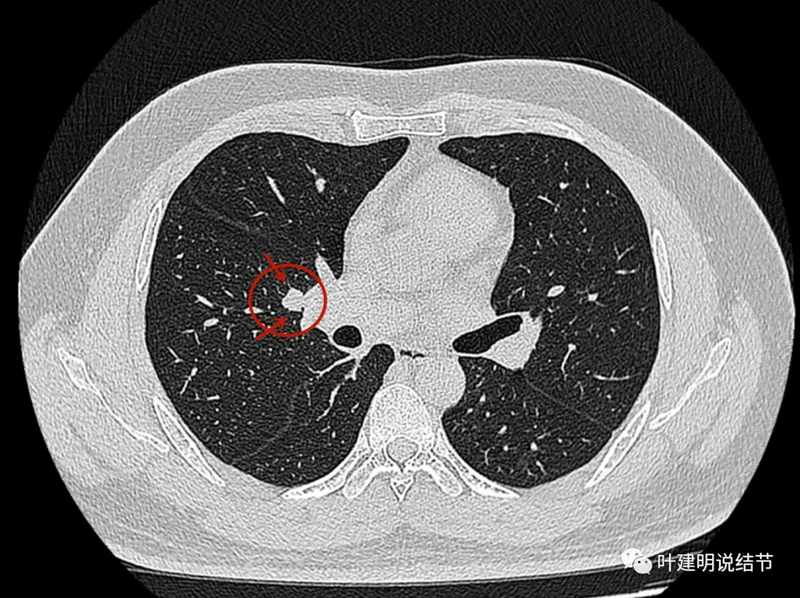

先看患者提供的2024年2月份的CT影像:

病灶出现,在右下叶支气管旁边,轮廓清楚,此层似磨玻璃密度。

表面似分叶状,密度不纯,邻近血管略有弯曲向病灶。

实性密度,边缘光滑,与背段支气管亚段贴着。